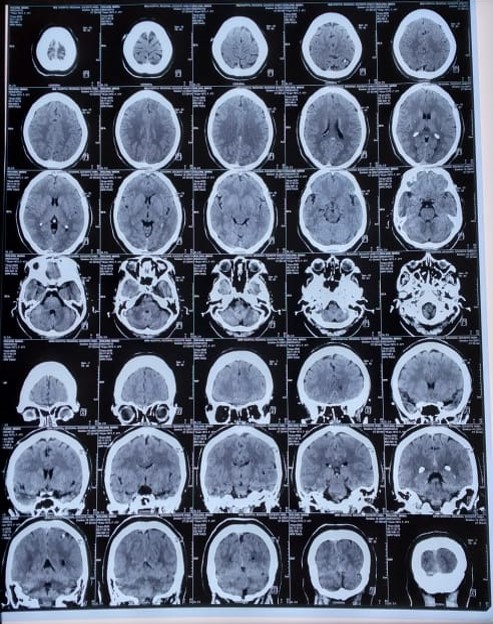

Julio del 2018: TAC simple de cráneo se evidencia cisticerco viable en región parietooccipital izquierda.

Febrero del 2019: TAC simple de cráneo se evidencia lesión quística. Diagnóstico de NCC en fase coloidal.

Diciembre 2020: TAC simple de cráneo se observa NCC en fase de calcificación nodular (Ver imagen 1).

En marzo del 2019 acude a cita médica en Neurología con TAC simple de cráneo, donde se evidencia NCC en fase coloidal, se decide continuar con la medicación.

En diciembre del 2020 en la TAC simple de cráneo se observa NCC en fase calcificada nodular.

Por lo que, se decide realizar una TAC simple de cráneo, y a su vez, iniciar tratamiento sintomático temporal hasta la aclaración del panorama. Más tarde, se obtiene los resultados de la TAC simple de cráneo, que confirma el diagnóstico de NCC, puesto que se logró evidenciar todos los estadios de la patología, que constituye un criterio absoluto propuesto por Del Brutto y cols. para el diagnóstico definitivo de esta entidad clínica22,23 (Ver tabla 1 y 2).

En los estudios de neuroimagen como la TAC simple de cráneo o RM, se pueden identificar las diferentes etapas de la NCC, las cuales consisten fisiopatológicamente en la presencia del quiste en el parénquima cerebral que evoluciona en cuatro etapas; en la etapa vesicular, el quiste se llena con un líquido claro, tiene una pared semitransparente delgada y un escólex opaco excéntrico de 4 a 5 mm que producen cambios inflamatorios escasos y generalmente son asintomáticos.24 Cuando el sistema inmunitario del huésped supera los mecanismos protectores del quiste, este comienza a degenerar, y la larva sufre una degeneración hialina y el líquido transparente del quiste se reemplaza con material gelatinoso, a esta fase se la conoce como coloidal. Posteriormente, el quiste se contrae, las paredes se reemplazan por nódulos linfoides focales y necrosis, y el escólex se transforma en gránulos mineralizados gruesos que forman la etapa nodular granular. Finalmente, el tejido de granulación se reemplaza por estructuras de colágeno y la calcificación que da lugar a la fase calcificada nodular, en este momento el edema cede, pero hay cambios astrocíticos perilesionales. Por otra parte, cuando los quistes se alojan fuera del parénquima cerebral, como sucede en los ventrículos, el espacio subaracnoideo o las cisternas, tienden a crecer de manera irregular según el espacio disponible y por lo general, provocan una fuerte respuesta inflamatoria. En ocasiones, los quistes se agrandan considerablemente, se vuelven en forma de racimos sin escólices y causan efectos de masa. Mientras que la hidrocefalia puede deberse a una obstrucción directa de las vías del líquido cefalorraquídeo (LCR) por quistes intraventriculares o secundaria a una obstrucción inflamatoria.10,25